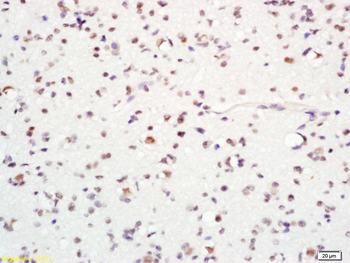

Tissue/cell: human glioma tissue, 4% Fixative-fixed and paraffin-embedded, Antigen retrieval: citrate buffer (0.01M, pH 6.0), Boiling bathing for 15 min, Block endogenous peroxidase by 3% Hydrogen peroxide for 30 min, Blocking buffer (normal goat serum) at 37℃ for 20 min, Incubation: Anti-MASH1 Polyclonal Antibody, Unconjugated (orb10143) 1:200, overnight at 4°C, followed by conjugation to the secondary antibody and DAB staining.